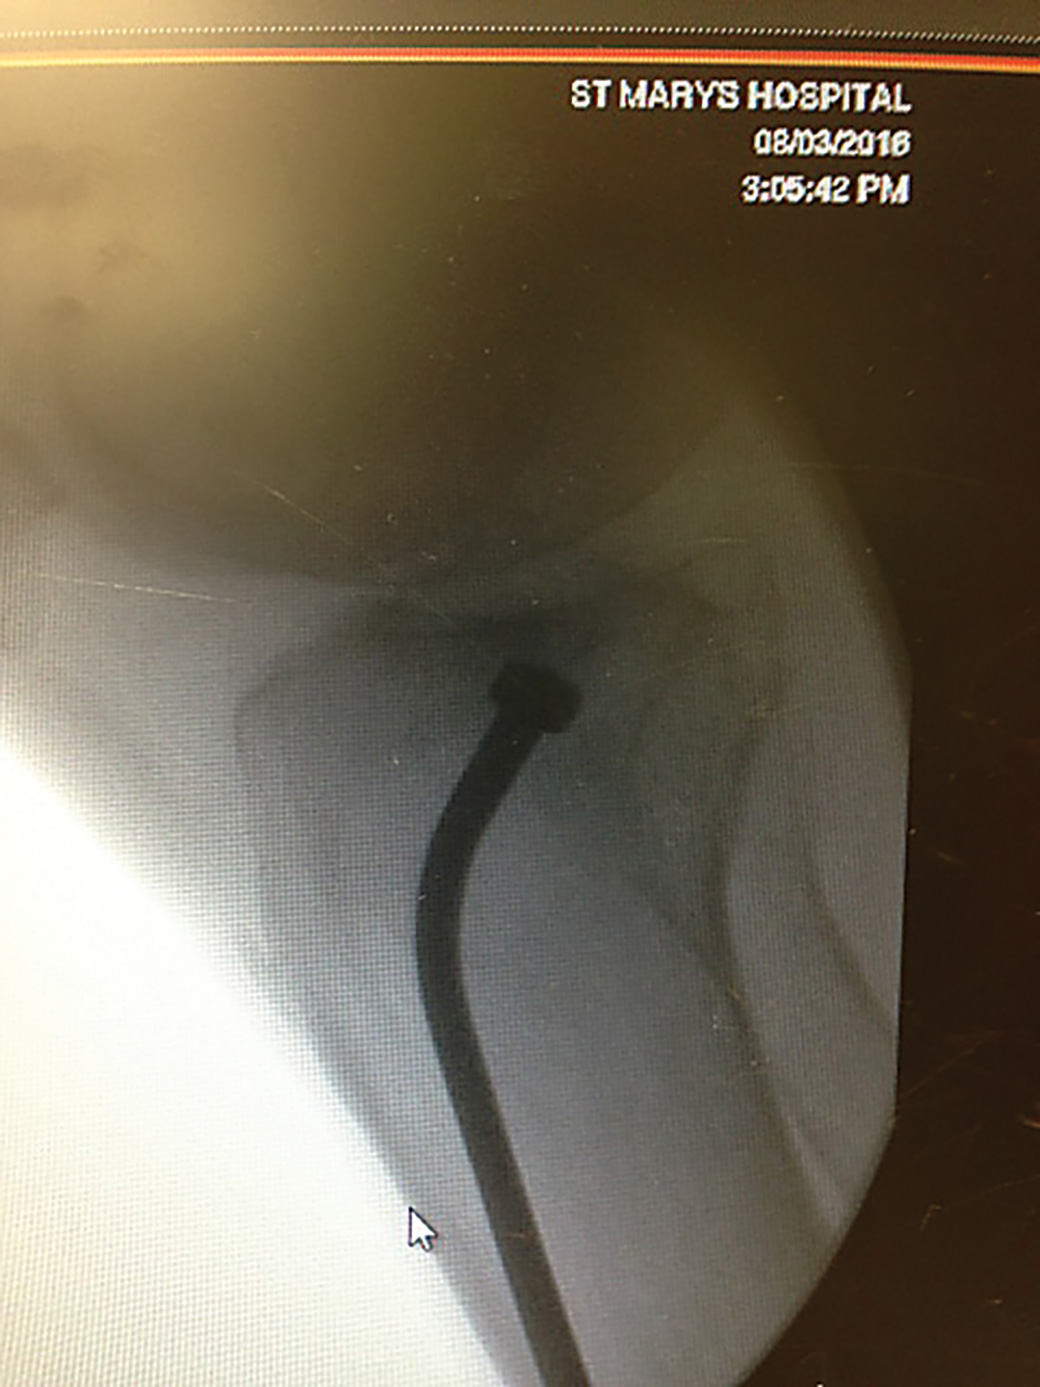

Designed to help with indirect reduction of a depressed tibial plateau fracture, and can be used with arthropscopic visualization and percutaneous fixation

Dimensions Overall Length: 11″ (27,9 cm) Tamp Diameter: 4,7 mm